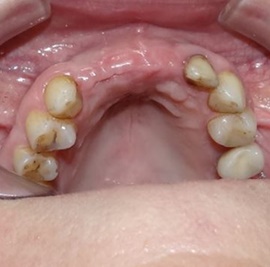

Chodzi tutaj nie tylko o przywrócenie funkcji narządu żucia, ale również zapewnienie trwałości takiego rozwiązania. Ponieważ jednak trwałość zależy w dużej mierze od odtworzenia poprawnych stosunków anatomicznych i histologicznych okazuje sie, że również w odcinkach bocznych uzębienia rehabilitacja funkcjonalna idzie w parze z estetyką.

Odbudowa lewego dolnego trzonowca.

Odbudowa prawego dolnego trzonowca.

Uzupełnienie trzonowców: szóstki i siódemki na implantach.

Odbudowa kości, dziąsła, implantacja, korony protetyczne, dwa prawe dolne trzonowce.

Obustronne braki skrzydłowe w żuchwie.

Obustronne braki skrzydłowe w szczęce.